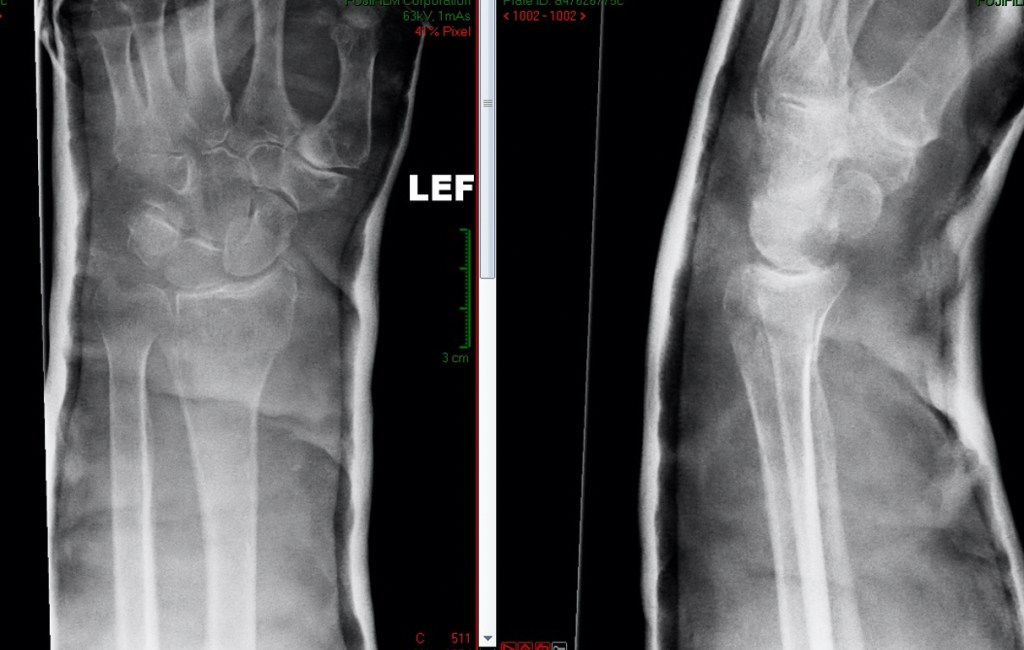

Fractures of the distal radius occur usually with a fall onto the outstretched hand. Often, the tip of the ulna will fracture at the same time.

2) UNSTABLE INJURY When the injury is unstable, it means that the broken parts of the bone do not move together, and often there is a gap on the xray between the bone ends, or an abnormal angulation between the bone ends.

Fractures of the distal radius produce immediate severe pain, swelling and often deformity of the wrist. It is usually very sore to move the wrist and fingers. Sometimes the fingers feel tingly or numb following a fracture.